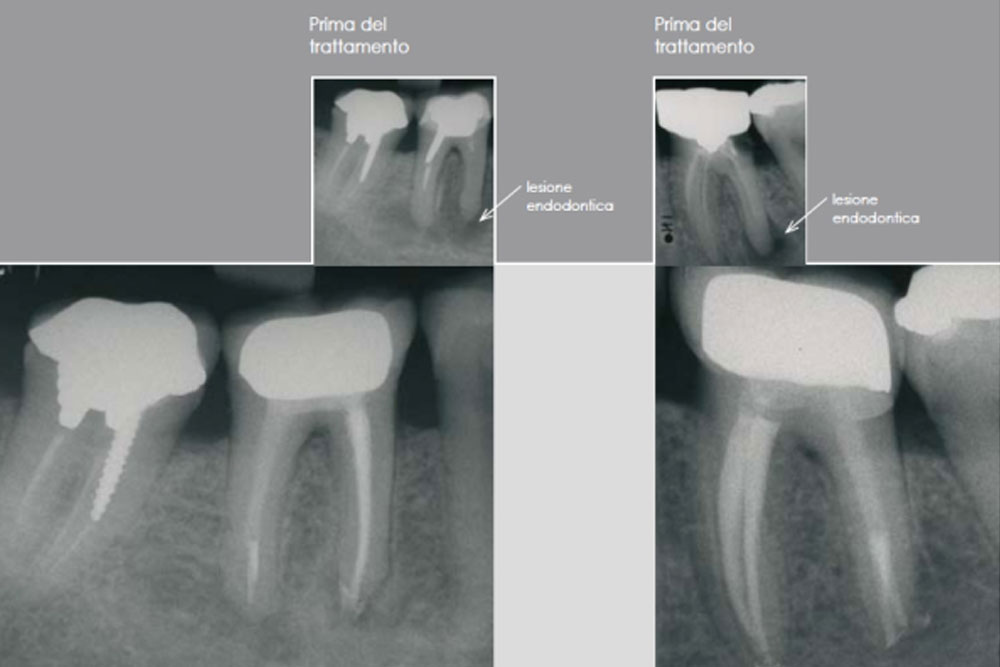

Si ricorre alla terapia endodontica qualora una lesione cariosa o traumatica al dente abbia determinato una alterazione irreversibile del tessuto pulpare, fino alla necrosi dello stesso. È possibile inoltre ricorrere a questa metodica qualora l’elemento dentario debba essere coinvolto in riabilitazioni protesiche che, a causa della notevole riduzione di tessuto dentale stesso, determinerebbero con alta probabilità un’alterazione pulpare irreversibile (necrosi pulpare per cause iatrogene).